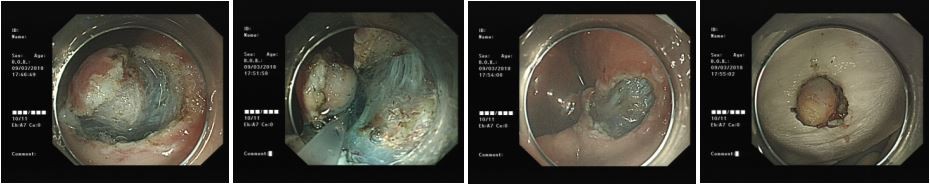

3.内镜下消化道黏膜切除术(EMR)黏膜剥离术(ESD)、黏膜下肿物挖除术(ESE)

胃肠道早期肿瘤的诊疗是我科近年重要发展方向,并取得较好的成绩。首先,我科开展了血清胃功能检查及胃肠镜精细检查进行食管、胃及大肠早癌筛查。其次,采用EMR及ESD技术对内镜下消化扁平状息肉、较大息肉及消化道癌前病变、早期癌等进行内镜下微创治疗。对于黏膜下的肿物则采用黏膜下挖除术(ESE)。

内镜下早癌的发现及内镜下黏膜剥离术(ESD)

内镜下黏膜下肿物挖除术(ESE)、荷包缝合技术